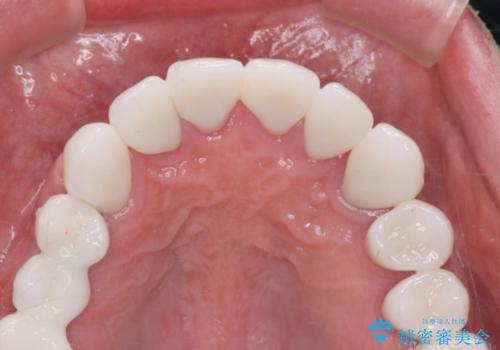

歯周外科を行い歯と歯槽骨・歯肉の関係を是正することで歯ぐきの状態を改善し、将来に亘り安定した歯周環境の維持を期待できるセラミック治療を実践します。

- 95.7万円(ジルコニアクラウン×6・仮歯×6・歯周外科)費用は治療当時の料金となります

歯ぐきが腫れたままの状態だと、違和感が生じるとともに常に炎症が存在する環境となってしまうので非常に好ましくない口腔内環境です。